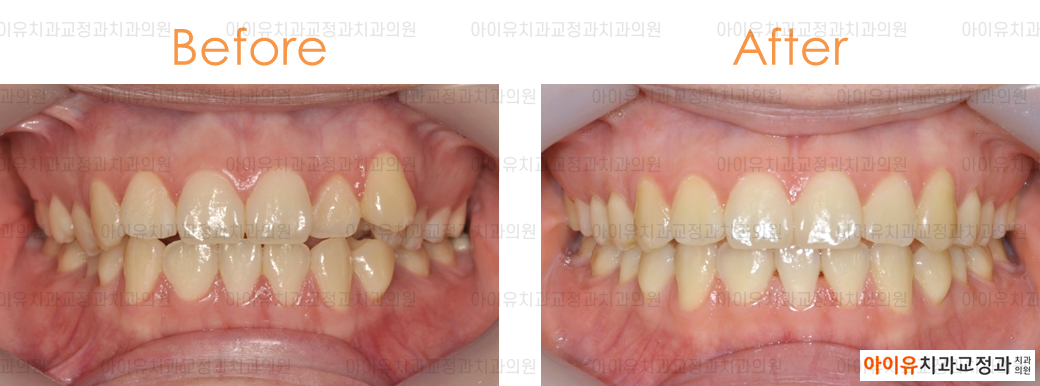

아래는 지난 몇 년간 울산 아이유치과에서 진행한 인비절라인 치료결과, 전후사진 중 일부입니다.

만 23세 / 송곳니 덧니 / 치료기간 1년 / 인비절라인 사용

위의 치료 결과에서 알 수 있듯 대부분의 경우에서 투명교정은 기존의 브라켓 교정과 동일한 효과를 얻을 수 있습니다.